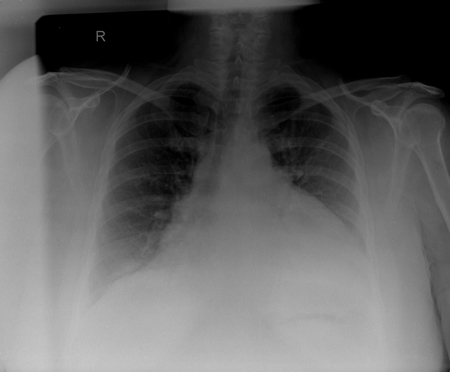

Assessment of pericardial effusion

CXR in a patient with a pericardial effusion showing typical findings of a water-bottle-shaped cardiac silhouette with a distinct, fat, pericardial fat stripe

From the collection of Dr Rajdeep Khattar